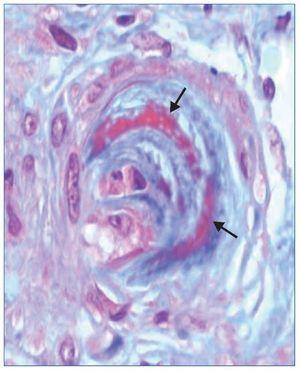

El tratamiento hipotensor consiguió controlar óptimamente la PA. De modo paralelo se normalizó la cifra de plaquetas y desaparecieron los signos de hemólisis. Tras ello se practicó una biopsia renal percutánea, que evidenció como signo más llamativo una afectación difusa y grave de las arteriolas renales, mostrando lesiones de endarteritis proliferativa (figura 2) y estrechamiento de las luces junto con lesiones de necrosis fibrinoide en la pared (figura 3). Los glomérulos presentaban cambios isquémicos sin presencia de trombos en la luz de los capilares. Se detectaban signos de discreta nefritis tubulointersticial. La inmunofluorescencia era negativa.

Figura 2. Fibrosis subintimal de la pared arteriolar con desdoblamiento de las fibras elásticas (flechas). Tinción de PAS (magnificación ×10).